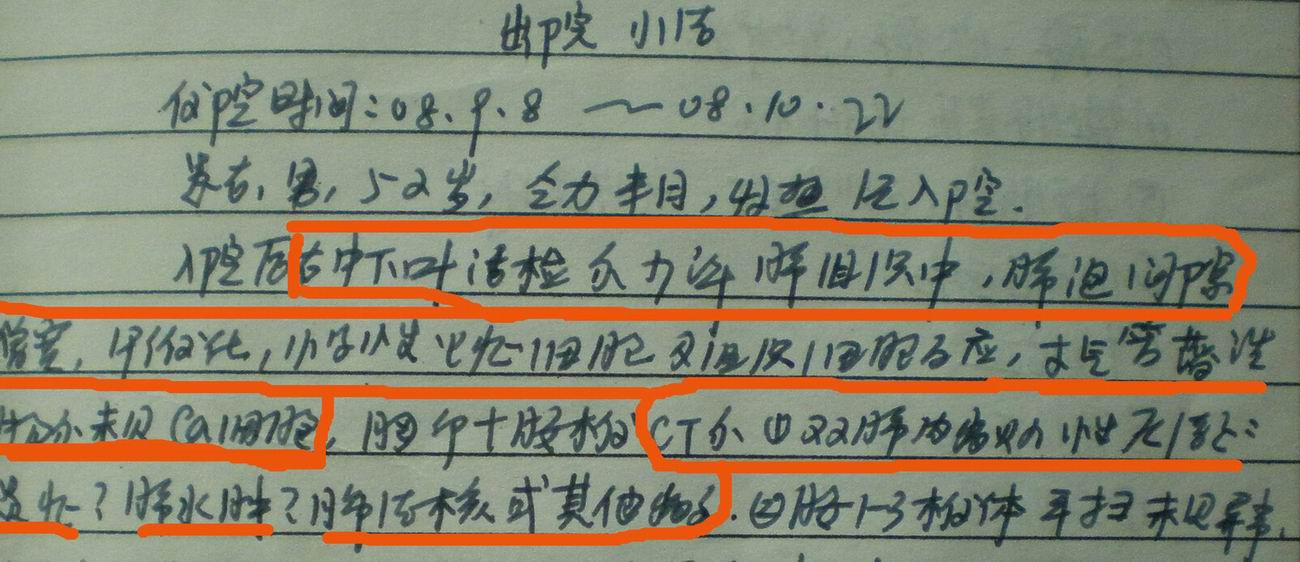

病人资料:男,52岁,因体癣股癣等皮肤病行激素治疗,因突然大剂量减药而起病,病情危急,9月8日曾在上级医院住院治疗,9月18日复查了ct片,相关检查及住院小结以图片资料上传。

上级医院住院小结:

我仔细看了下病人的出院小结,当时情况危急,诊断里有1型呼衰。心包周围的是脂肪密度。结合三次ct扫描的图象分析,个人认为:1、病人目前肺部病灶基本消失,双侧胸腔内少量积液,抗结核治疗才一个多月,就算是结核,抗结核治疗有效果,为何效果如此好,一点纤维灶的痕迹都没有呢,再就是患者做过气管镜检查及活检、痰检均未找到结核的证据。所以不支持结核的诊断。